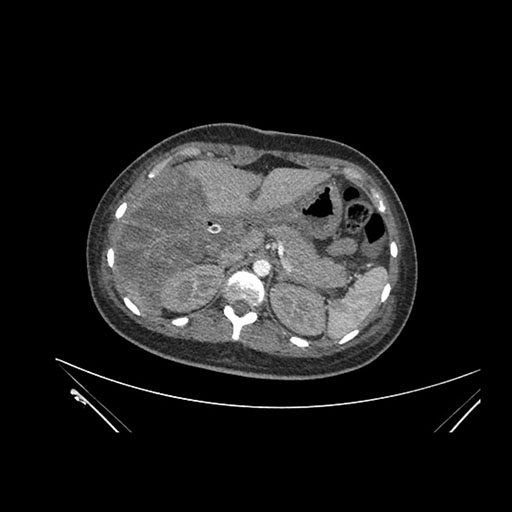

Axial Arterial

Axial Venous

Imaging analysis

Based on initial findings, which issue(s) would you be most concerned about?